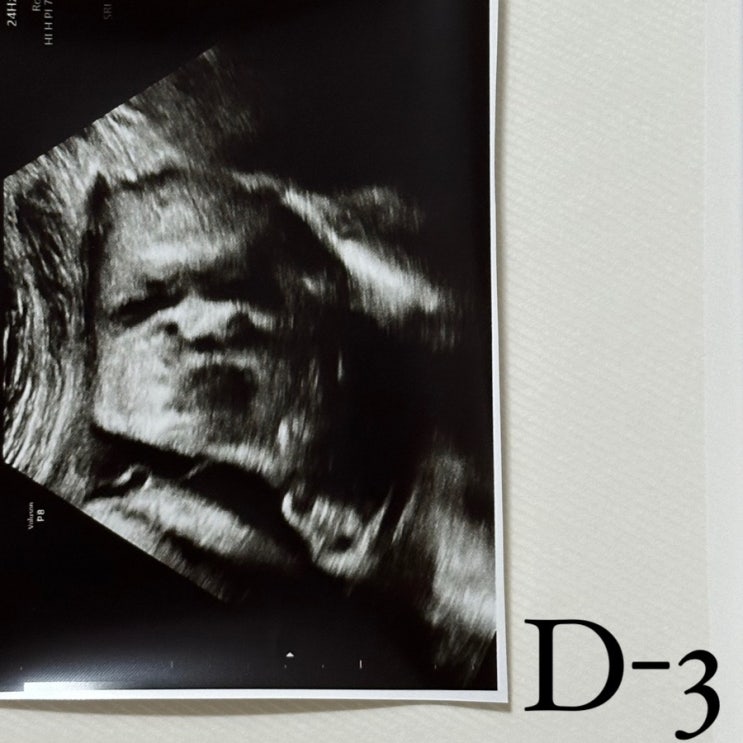

경산모, 일산차병원 제왕절개 수술 3일차/단일제대동맥 초음파(홍기림교수님)

벌써 3일차-! 훗배앓이 때문에 두번째 제왕절개가 더 아프다고 생각했는데 회복속도는 더 빠른듯? 하루하루...